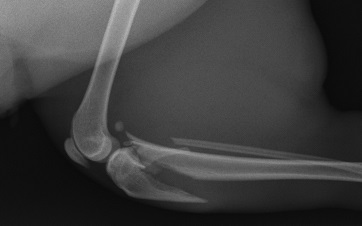

Steinmann intramedullary pins, K-wires can still be used for certain oblique diaphyseal fractures and condylar and avulsion fractures respectively.